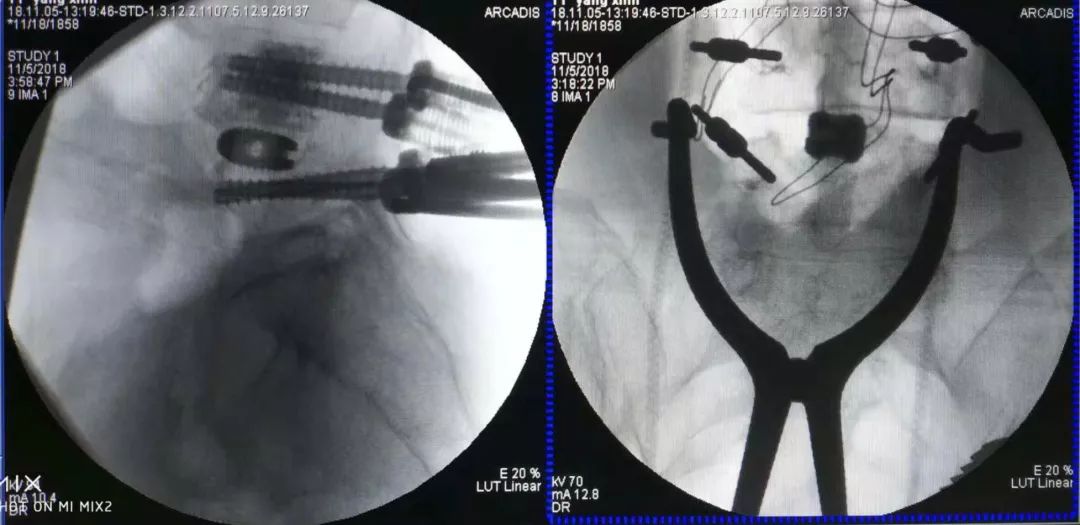

术中情况

术前术后CT对比

术后CT示腰4-5椎间融合器固定在位,腰4/5椎体内骨水泥填充于螺钉周围,螺钉固定妥。